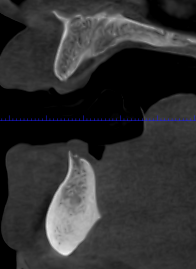

Las extracciones complejas, especialmente de terceros molares inferiores, suponen un reto quirúrgico cuando existe cercanía entre las raíces dentarias y